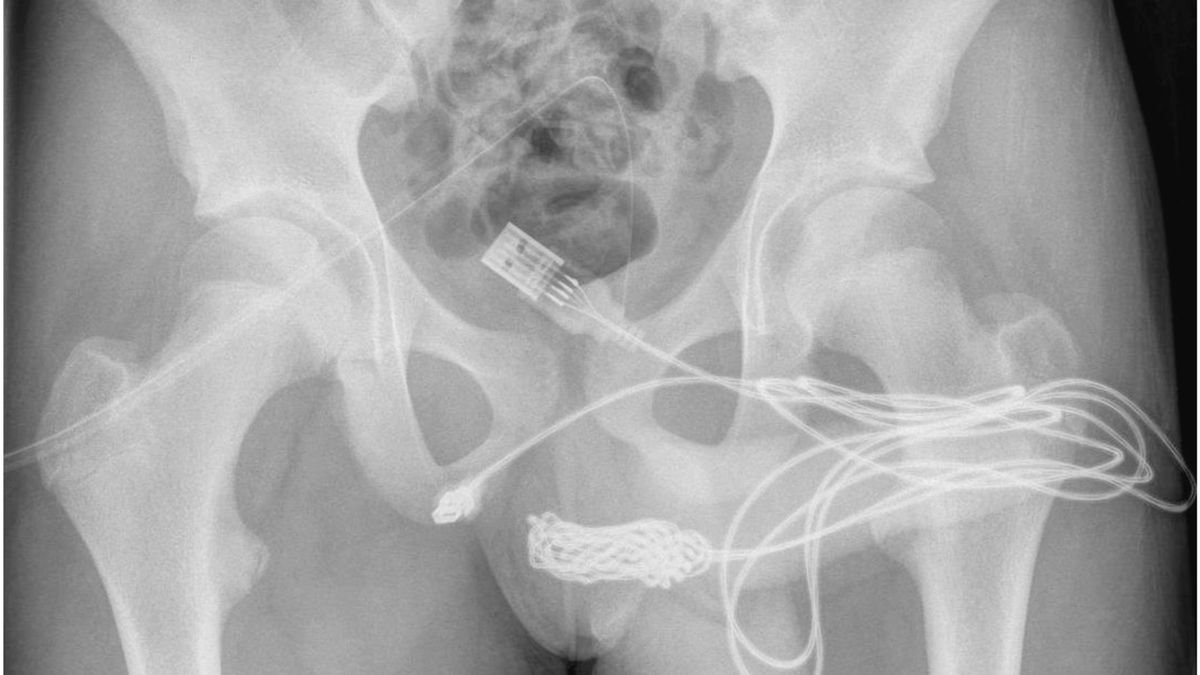

Një adoleshenti iu nevojit ndërhyrja e mjekëve pasi një kabëll USB i ngeci në penis.

15-vjeçari britanik po përpiqej të maste brendinë e organit të tij gjenital si formë “eksperimenti social”, por u ngatërrua në një nyje dhe nuk mundi ta nxirrte.

Në raportin  e mjekvëe, shkruhej se djali nuk kishte historik të çrregullimit të shëndetit mendor. Ata nuk mundën ta hiqnin kabëllin me shufër metalike për shkak të nyjeve të formuara, ndaj iu desh ta fusnin në operacion.

Mes gjenitaleve dhe anusit, ata futën një tub dhe kateterë që të nxirrnin kabëllin e bllokuar.